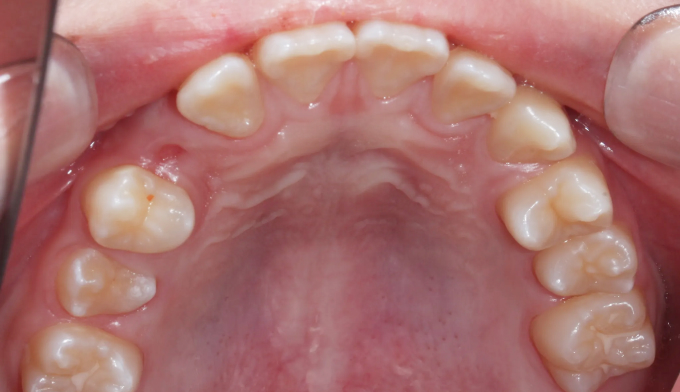

이번 케이스에서는 위쪽 송곳니의 맹출경로이상, 아래쪽 작은어금니는 작은 물혹으로 인해 맹출 경로에 문제가 생겨 교정을 진행한 경우입니다.

물혹을 제거하고 치아 교정장치를 부착하여 간단히 배열하였습니다.

총 교정기간은 11개월 입니다.